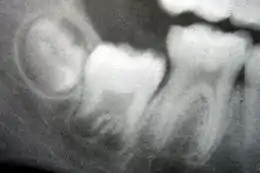

Éruption dentaire

L'éruption des dents se produit lorsque les dents pénètrent dans la cavité buccale et deviennent visibles. Même si les chercheurs conviennent que l'éruption des dents est un processus complexe, il y a peu d'accord sur l'origine du mécanisme qui contrôle cette éruption[21]. Parmi les théories communément admises et qui ont été réfutées au fil du temps, on peut citer :

Bien que l'éruption des dents se produise à différents moments selon les personnes, une chronologie générale des éruptions dentaires existe. En général, les humains ont 20 dents de lait et 32 dents permanentes[25]. L'éruption comporte trois étapes. La première, connue sous le nom stade de la dentition primaire, se produit lorsque les dents de lait sont visibles. Une fois la première dent permanente sortie dans la bouche, les deux types de dents sont présentes dans la bouche : c'est la dentition mixte. Après que la dernière dent de lait est tombée par un processus connu sous le nom d'exfoliation, on est au stade de la dentition permanente.

La dentition primaire commence à l'arrivée des incisives centrales de la mandibule, habituellement à huit mois, et dure jusqu'à ce que les premières molaires permanentes apparaissent dans la bouche, généralement avant six ans[26]. Les dents primaires sortent dans l'ordre suivant : (1). incisive centrale, (2) incisive latérale, (3) la première molaire, (4) canine et (5) deuxième molaire[27]. En règle générale, il y a quatre éruptions de dents tous les six mois ; les dents mandibulaires sortent avant les dents maxillaires et l'éruption des dents se produit plus tôt chez les filles que les garçons[28]. Au cours de la dentition primaire, les bourgeons dentaires des dents permanentes se développent sous les dents primaires, sur le versant lingual ou palatin.

La dentition mixte commence lorsque la première molaire permanente apparaît dans la bouche, généralement à six ans, et dure jusqu'à ce que la dernière dent de lait soit perdue, le plus souvent à onze ou douze ans[29]. Les dents permanentes du maxillaire sortent dans un ordre différent des dents permanentes de la mandibule. Les dents du maxillaire sortent dans l'ordre suivant : (1) première molaire (2) incisive centrale, (3) incisive latérale, (4) première prémolaire, (5) deuxième prémolaire, (6) canine, (7) deuxième molaire et (8) troisième molaire. Les dents de la mandibule sortent dans l'ordre suivant : (1) première molaire (2) incisive centrale, (3) incisive latérale, (4) canine, (5) première prémolaire, (6) deuxième prémolaire, (7) deuxième molaire, et (8) troisième molaire. Comme il n'y a pas de prémolaires dans la dentition primaire, les molaires primaires sont remplacées par les prémolaires permanentes[30]. Si les dents primaires sont perdues avant que les dents permanentes ne soient prêtes à les remplacer, les dents postérieures peuvent se déplacer vers l'avant et réduire l'espace disponible pour la future dent[31]. Cela peut provoquer des chevauchements et/ou des malpositions des dents permanentes, ce qu'on appelle généralement « malocclusion ». Une orthodontie peut être alors nécessaire dans de telles circonstances pour réaligner les dents.

La dentition permanente commence lorsque la dernière dent de lait est tombée, habituellement à 11 à 12 ans, et dure jusqu'à la fin de la vie d'une personne ou jusqu'à ce que toutes les dents soient perdues (édentation). Durant cette phase, les troisièmes molaires (aussi appelées dents de sagesse) sont souvent extraites en raison d'infections locales, de douleurs à l'éruption ou d'impactions dentaires. Les principales raisons de la perte des dents sont la carie et la maladie parodontale[32].